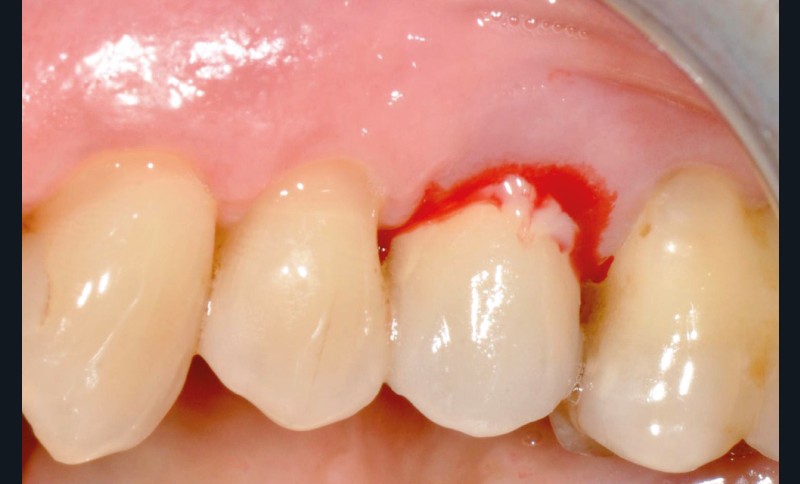

- Péri-implantite diagnostiquée en 2020